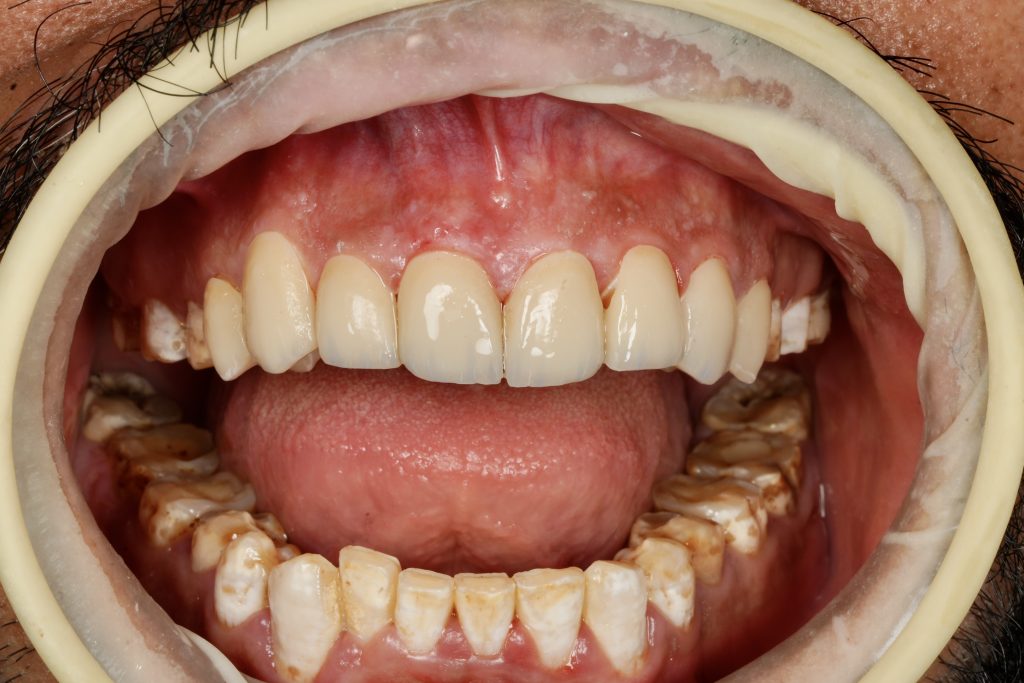

Using silicone indexes derived from the mock-up, controlled minimal-thickness veneer preparations (0.3–0.5 mm) were carried out under microscope magnification to ensure uniform reduction and margin clarity (Fig 2). Finish lines were placed juxta-gingivally with soft-tissue protection using Teflon and double-cord isolation.